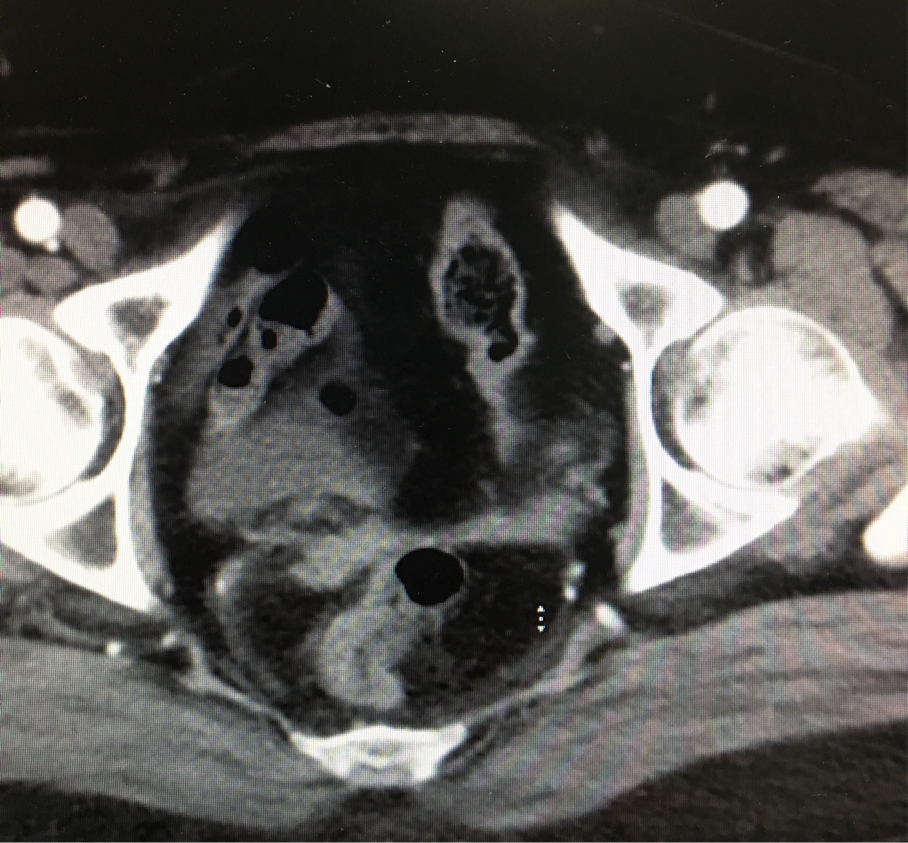

陈主任详细询问了患者的病史,仔细查看了曾阿姨的检查报告,考虑患者就诊多家医院,一年来多次化疗病情无好转,化疗反应大,患者心理负担重,陈主任耐心向患者解释病情,并告诉患者不用担心,给患者办理住院手续。结合曾阿姨的病史,陈主任在给患者安排了常规检查后,立即启动了肿瘤MDT讨论,并邀请患者家属现场听取专家建议。陈主任说:“患者属于肿瘤复发,既往有手术史,腹腔内结构比一般人复杂,而且患者的肿瘤紧邻直肠、输尿管等,增加手术难度。”

资料照

图片